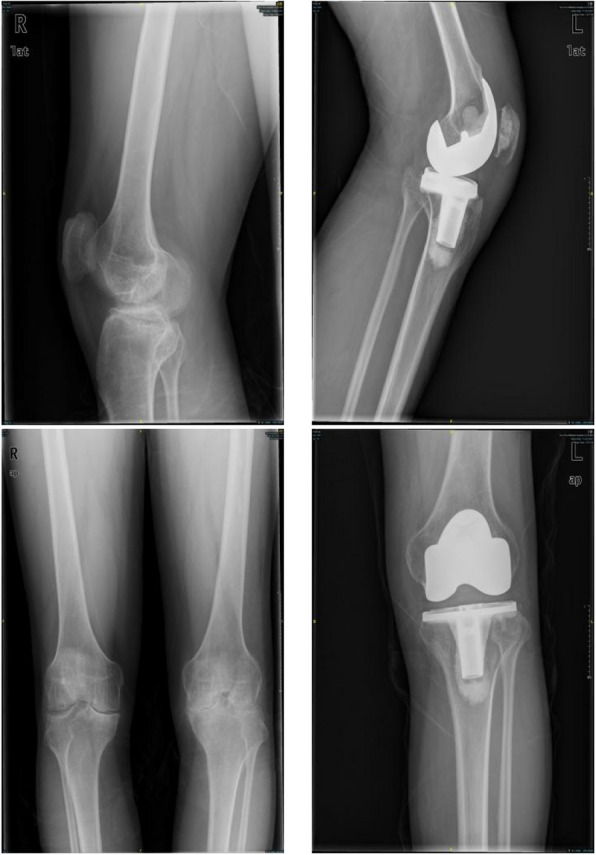

Methods: Between January 2008 and December 2021, 22 male patients with ankylosed knees in the extended position due to hemophilia underwent TKA. The average age of the patients was 41.3 years (range, 19 to 52 years), and the average hospital stay was 33.4 days (range, 14 to 50 days). TKA was performed using quadriceps tendon Z-lengthening plasty, staged osteotomy, and comprehensive soft-tissue release. A variety of methods were used to evaluate the postoperative clinical outcomes and complications, including range of motion (ROM) assessment, Visual Analogue Scale (VAS), Knee Society Score (KSS), and the Western Ontario and McMaster Universities Osteoarthritis Index (WOMAC).

Results: At the last follow-up, the average KSS increased from 75.14 ± 34.63 before surgery to 148.41 ± 27.74 (P < 0.001), the ROM increased from 0 to 86.14 ± 24.69 (P < 0.001), the WOMAC score changed from 28.05 ± 11.20 before surgery to 10.82 ± 11.00 (P < 0.001), and the average VAS score decreased from 2.86 ± 1.86 to 0.73 ± 1.20 (P < 0.001).

Conclusion: Although the recovery of range of motion is lower than normal and there is a relatively high incidence of complications, TKA can still significantly improve the flexion and extension functions, mobility, and quality of life of patients with ankylosed knees.